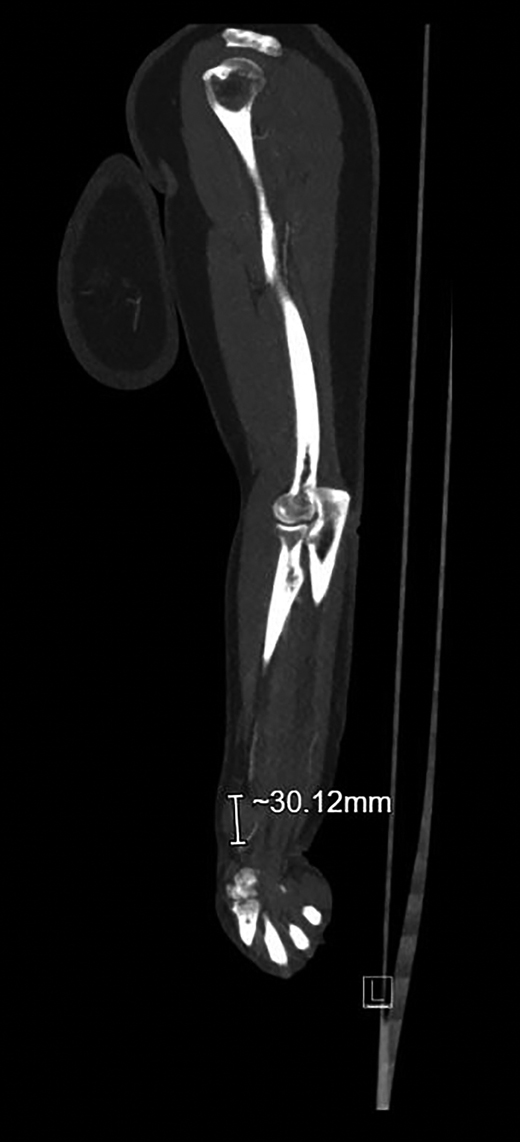

Op de echo wordt ter plaatse van de zwelling een vaatstructuur van > 2 cm gezien met een pulserende flow [figuur 3]. Er wordt direct een CT-angiogram gemaakt, waarop tegen de a. radialis een bolvormige laesie met een diameter van 3 cm te zien is [figuur 4]. De laesie kleurt volledig aan, passend bij een aneurysma spurium. In verband met de pijnklachten wordt mevrouw De Greef verwezen naar de Spoedeisende Hulp. Aldaar wordt de antistolling stopgezet in de verwachting dat de zwelling zal stollen en het stolsel langzaam zal worden opgeruimd. Op de controle-echo’s na 2 weken blijkt echter nog steeds flow aanwezig. Hierop krijgt mevrouw De Greef een trombine-injectie toegediend in de zwelling. Na 6 weken is vrijwel het gehele aneurysma geresorbeerd. Vermoedelijk was het ontstaan ten gevolge van de hartkatheterisatie enige maanden geleden.

Figuur 4 | CT-angiografe van een aneurysma spurium